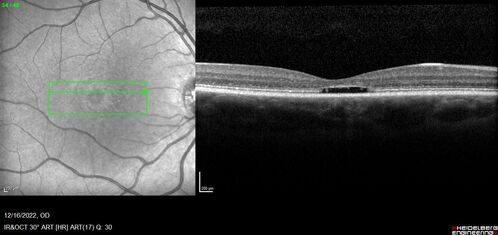

Stargardt Disease - Very Mild - 24 year old

This patient has 3 different ABCA4 mutations. His mother and sister have stargardts and his father has RP. His sisters images are also on Retinagallery.com